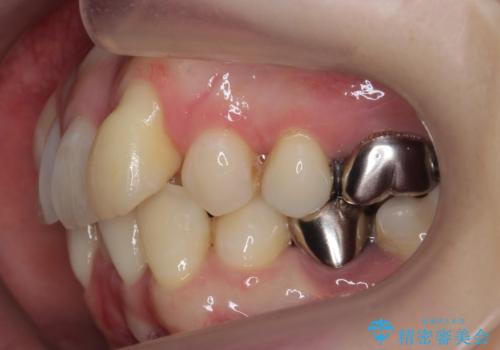

- 八重歯を主訴に来院。他院で全体ワイヤー矯正、4本抜歯で3-4年かかるかもしれないと説明を受けたとのこと。

そこまで時間がかかるのはどうかな、でも八重歯は気になるというご相談でした。

八重歯の部分は抜歯し、奥に入っていた前歯を前に移動させました。

下の前歯は生まれつき3本だったため、さらに2本下を抜くとなると3本少なくなってしまうため、下の前歯を一本お取りして最小限の抜歯としました。

今回は特に左上の犬歯は歯肉退縮して根が露出していたのもあり、抜歯をお勧めしました。